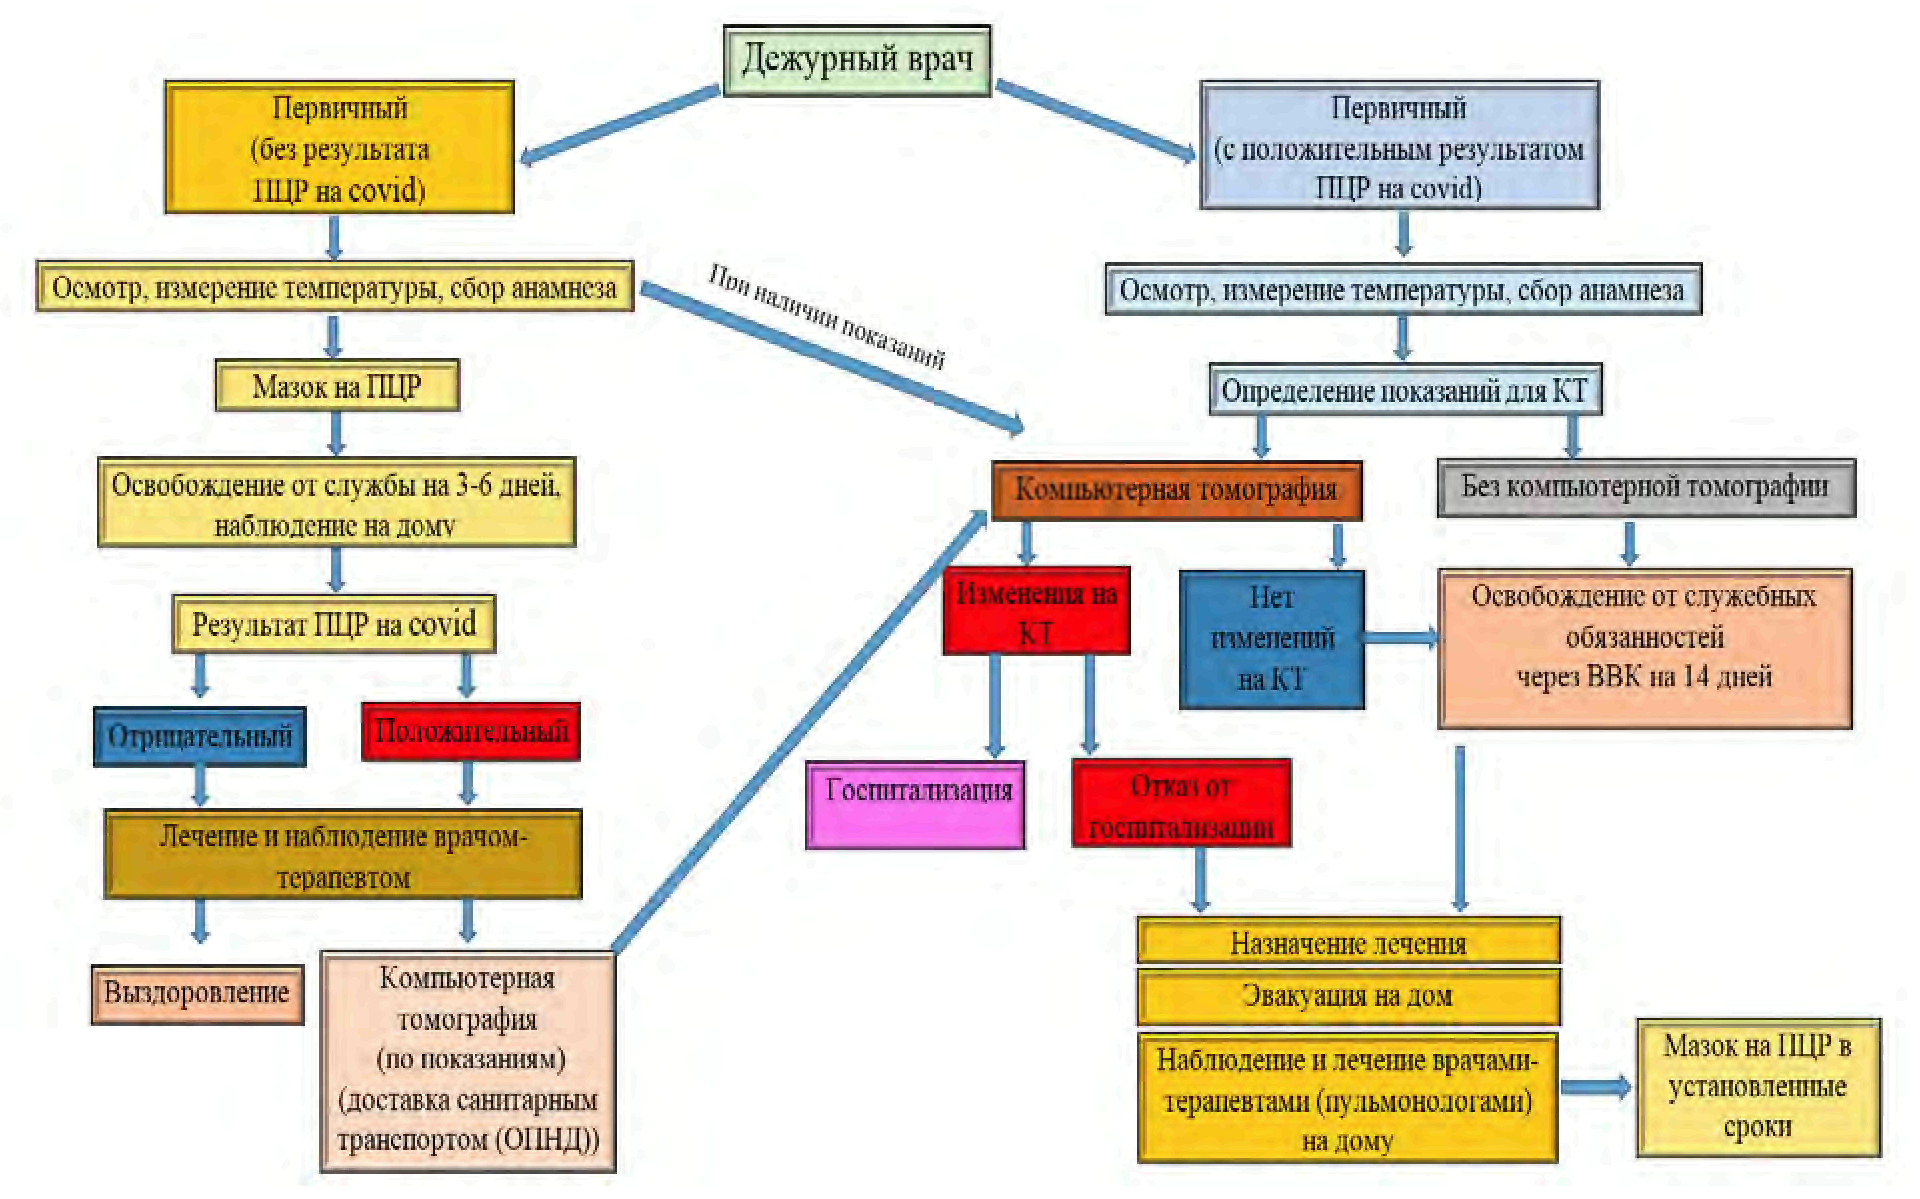

1. До момента получения положительного результата лабораторного исследования на наличие РНК SARS-CoV-2 с применением методов амплификации нуклеиновых кислот, пациент наблюдается как подозрительный на COVID-19 случай в соответствии с приложением N 2 к настоящим Методическим рекомендациям.

2. После получения от ЦГСЭН района ответственности или иной уполномоченной организации информации о положительном результате лабораторного обследования военнослужащего на COVID-19, уполномоченное лицо военно-медицинского подразделения, части или организации Министерства обороны Российской Федерации, где военнослужащий состоит на медицинском обеспечении:

- организует в случае наличия показаний для проведения КТ ОГК доставку военнослужащего санитарным транспортом (санитарным автомобилем отделения неотложной медицинской помощи военной поликлиники) к месту проведения исследования.

- организует при наличии изменений на КТ ОГК немедленную госпитализацию военнослужащего выездной медицинской бригадой в военный госпиталь, при его отсутствии на территории, в медицинскую организацию, уполномоченную оказывать медицинскую помощь пациентам с COVID-19 в стационарных условиях. В случае отказа военнослужащего от госпитализации организует лечение и наблюдение на дому;

- организует при отсутствии изменений на КТ ОГК обследование и лечение, наблюдение на дому (в изоляторе) с освобождением от исполнения должностных и специальных обязанностей, занятий и работ (с представлением на ВВК при наличии оснований).

4. При первичном обращении в подтверждённых и вероятных случаях заболевания военнослужащему назначается лечение в соответствии с актуальной версией Временных методических рекомендаций "Профилактика, диагностика и лечение новой коронавирусной инфекции (COVID-19)", утверждаемых уполномоченным должностным лицом Министерства здравоохранения Российской Федерации, с учетом алгоритма принятия лечащим врачом решения об оказании медицинской помощи в амбулаторных и (или) стационарных условиях (приложение N 5 к настоящим Методическим рекомендациям).